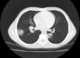

Cavitating pneumonia

Pneumonia is an inflammatory condition of the lung primarily affecting the small air sacs known as alveoli. Symptoms typically include some combination of productive or dry cough, chest pain, fever and difficulty breathing. [Source: Wikipedia ]